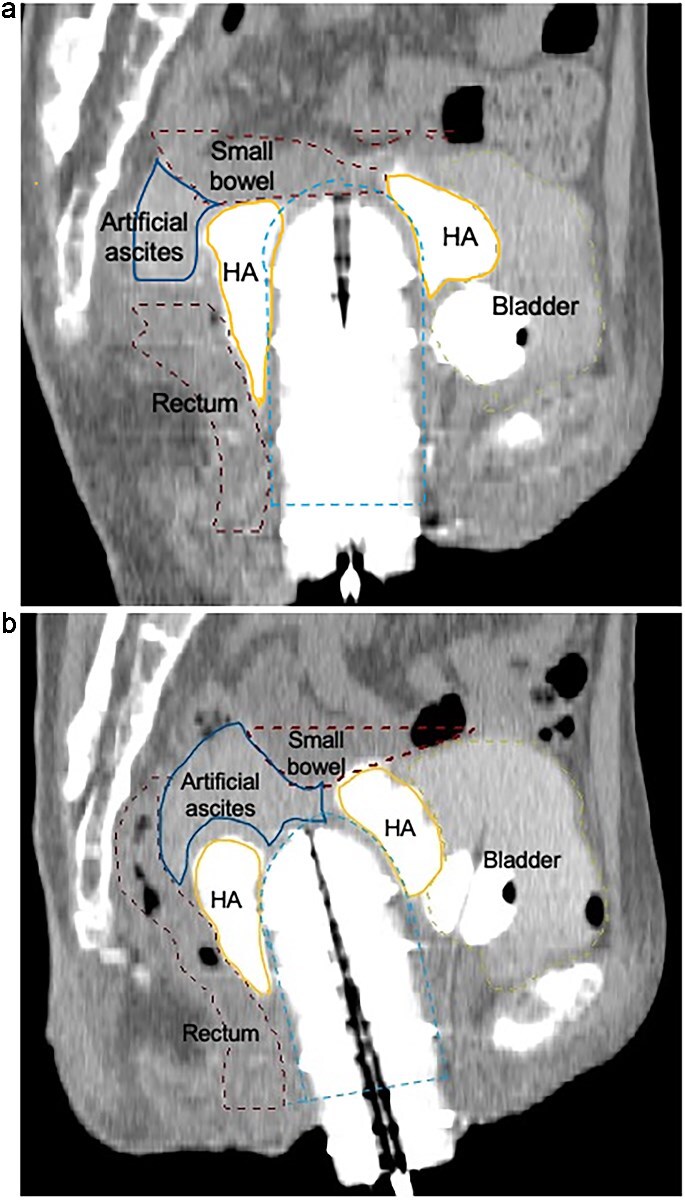

In recurrent gynecologic malignancies following prior pelvic irradiation, definitive radiation therapy is often precluded by cumulative dose constraints to adjacent organs at risk (OARs), and patients may be left with only highly invasive surgical options such as total pelvic exenteration. While some institutions have explored displacement techniques such as artificial ascites or hyaluronic acid gel injection, these approaches are not widely adopted and frequently fail to ensure consistent and stable separation of OARs. We report the first clinical use of Neskeep®, a bioabsorbable polyglycolic acid (PGA) spacer, in high-dose-rate (HDR) brachytherapy for recurrent cervical cancer after prior pelvic radiation. A woman in her 40s with prior hysterectomy and HDR brachytherapy for cervical intraepithelial neoplasia grade III developed vaginal stump recurrence 4 years later. Laparoscopic placement of the PGA spacer was performed to achieve durable displacement of the small bowel, followed by eight fractions of HDR brachytherapy. Hyaluronic acid gel was also injected during each fraction to displace the bladder and rectum. The spacer maintained position and volume throughout treatment without complications. Dose-volume analysis showed a marked reduction in small bowel D₂cc (mean equivalent dose in 2 Gy fractions (EQD₂): 121.6 cGy) compared to the initial treatment (606.0 cGy), while the spacer itself received a mean D₂cc of 690.3 cGy. MRI confirmed complete response at 2 months, with no adverse events observed at that time point. The PGA spacer enabled safe, curative reirradiation in a case that would otherwise be unsuitable for further radiation therapy.